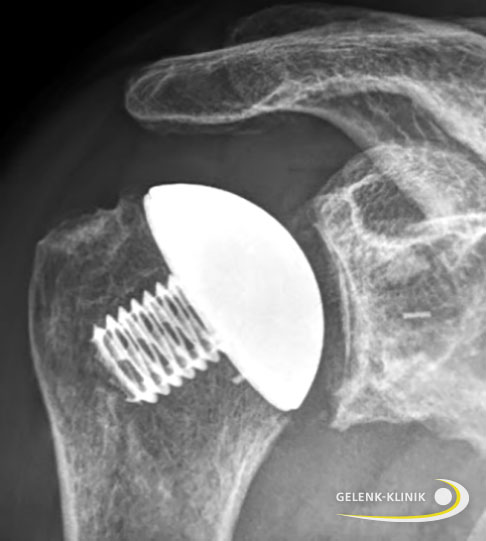

Die Sehnen und die grundlegende Anatomie des ursprünglichen Gelenks werden bei der Operation einer Kappenprothese beibehalten. Der Spezialist ersetzt nur die zerstörten Gelenkflächen, indem er am Oberarmkopf eine metallische Kappe aufsetzt. Die abgenutzte Pfanne erneuert er durch ein Polyethylen-Inlay. Gleichzeitig entfernt der Operateur störende Knochenanbauten, damit die Metallkappe optimal auf dem Polyethylen-Inlay gleiten kann. Der Halbkugel-ähnliche Charakter der Kappe ermöglicht den Betroffenen einen hohen Bewegungsumfang.

Schematische Darstellung einer Kappenprothese. Sie besteht aus zwei Komponenten: einer zementfrei fixierten Hohlschraube im Oberarmkopf und einer Pfannenkomponente aus Kunststoff. Die Sehne des Musculus supraspinatus und der Deltamuskel werden in ihrer anatomischen Lage nicht verändert. Der Drehpunkt des Schultergelenks bleibt wie der Abstand zwischen Oberarm und Schulterdach (Akromion) unverändert. © Gelenk-Klinik

Knochensparender Ersatz der Gelenkflächen von Oberarmkopf und Gelenkpfanne mithilfe einer Kappenprothese. Dieses Modell der Schulterprothese erhält die ursprüngliche Anatomie der Schulter. Die Glenoidkomponente aus Kunststoff ist im Röntgen kaum sichtbar. © Gelenk-Klinik